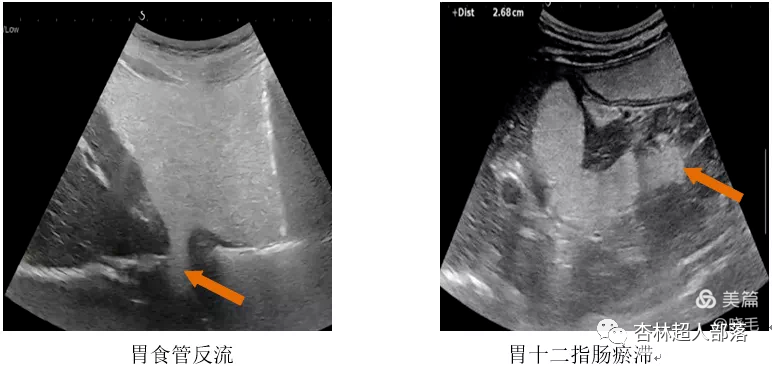

下面我们看看胃肠超声扫描出来的

这些典型病例图像吧。